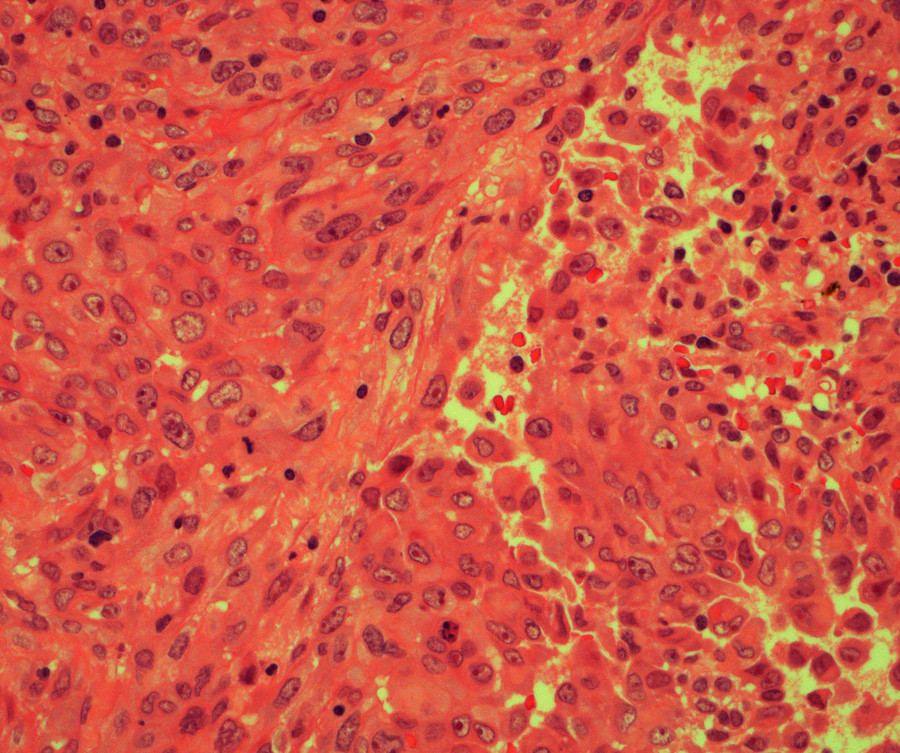

Det ble så i narkose tatt dyp sylinderbiopsi (6 mm i diameter) fra tumoren, med materiale fra både bløtvev og bein. Biopsien viste epiteloide og spolformede celler med lav mitoseaktivitet (fig 4). Immunhistokjemisk undersøkelse viste positiv reaksjon for AE1/AE3, EMA, CD 34, CD99 og CK19.

Samlet passet dette med epiteloid sarkom. Nå overtok sarkomgruppen videre utredning.

Vanligvis fremstår epiteloide sarkomer som faste, hudfargede, indolente knuter. De kan ulcerere og affisere subcutis og dypere bindevev som muskelfascie og sener. Histologisk har epiteloide sarkomer nodulært vekstmønster og viser både epitelial og mesenkymal differensiering. Tumor mistolkes ofte som en kronisk inflammatorisk prosess, nekrotiserende granulom eller fibrohistiocyttære tumorer (9, 10).